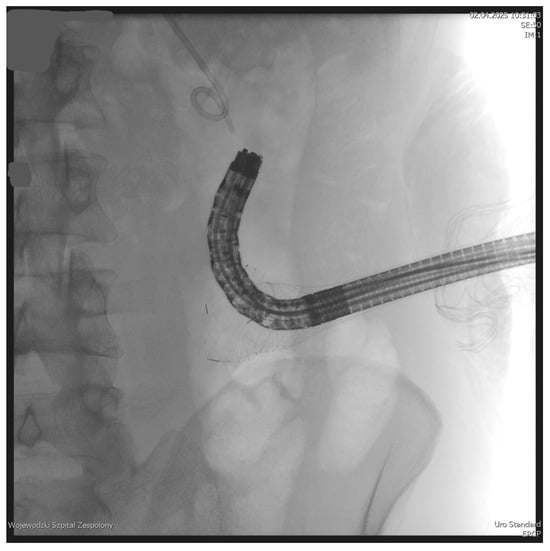

The PEN procedure was performed under general anesthesia with endotracheal intubation in the supine position. Percutaneous endoscopic necrosectomy was performed under the guidance of ultrasound (using a Logiq P9, convex C1-6 MHz probe) and fluoroscopy. Following the establishment of percutaneous drainage, Cook Medical Acrobat 2 AWG2-35-45 guidewire was inserted and looped inside the lumen of the necrotic collection (Figure 1 and Figure 2) to be followed by implantation of a fully coated self-expandable Evolution® esophageal controlled-release stent 120 mm or 150 mm in length and 20 mm in diameter (Figure 3 and Figure 4). A flexible Evis Exera III CF-H190L endoscope–gastroscope (Olympus) was then inserted into the necrotic collection through the lumen of the esophageal stent, and a percutaneous endoscopic necrosectomy procedure involving mechanical removal of necrotic tissue from the collection under direct endoscopic image guidance was performed (Figure 5, Figure 6 and Figure 7). A Dormia basket (Figure 8) was used to remove necrotic tissue. In the course of the percutaneous endoscopic necrosectomy procedure, the necrotic collection was extensively flushed with physiological saline, and the contents from the reservoir were aspirated. The PEN procedure was considered complete upon removal of demarcated necrotic tissues or upon bleeding from the inflammatory granulation tissue within the necrotic collection. If subsequent percutaneous endoscopic necrosectomy procedures were required in the same patient, the esophageal stent was left in the percutaneous position, and one or two 16 Fr silicone drains (depending on the size of the collection) were inserted into the lumen of the necrotic collection through the stent to maintain patency. The drain(s) were used to flush the collection with 100 mL of physiological saline 6 times a day. Following the completion of endoscopic treatment using percutaneous access, the esophageal stent was removed, and the stenting site was secured with a stoma bag to drain the remaining contents from the residual necrotic collection (Figure 9).

Figure 1. Looped guidewire within the lumen of the WOPN cavity. Source: Department of General, Gastroenterological, and Oncological Surgery, L. Rydygier Regional Hospital in Toruń.

Figure 2. Guidewire percutaneously inserted into the lumen of the WOPN collection. Source: Department of General, Gastroenterological, and Oncological Surgery, L. Rydygier Regional Hospital in Toruń.